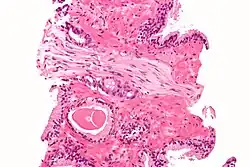

Tumorbefallener Lymphknoten bei einem Kolonkarzinom, also Stadium mindestens pN1

N (für lateinisch Nodus lymphaticus bzw. englisch Node = (Lymph)knoten) beschreibt das Vorhandensein bzw. das Fehlen von regionären Lymphknotenmetastasen.